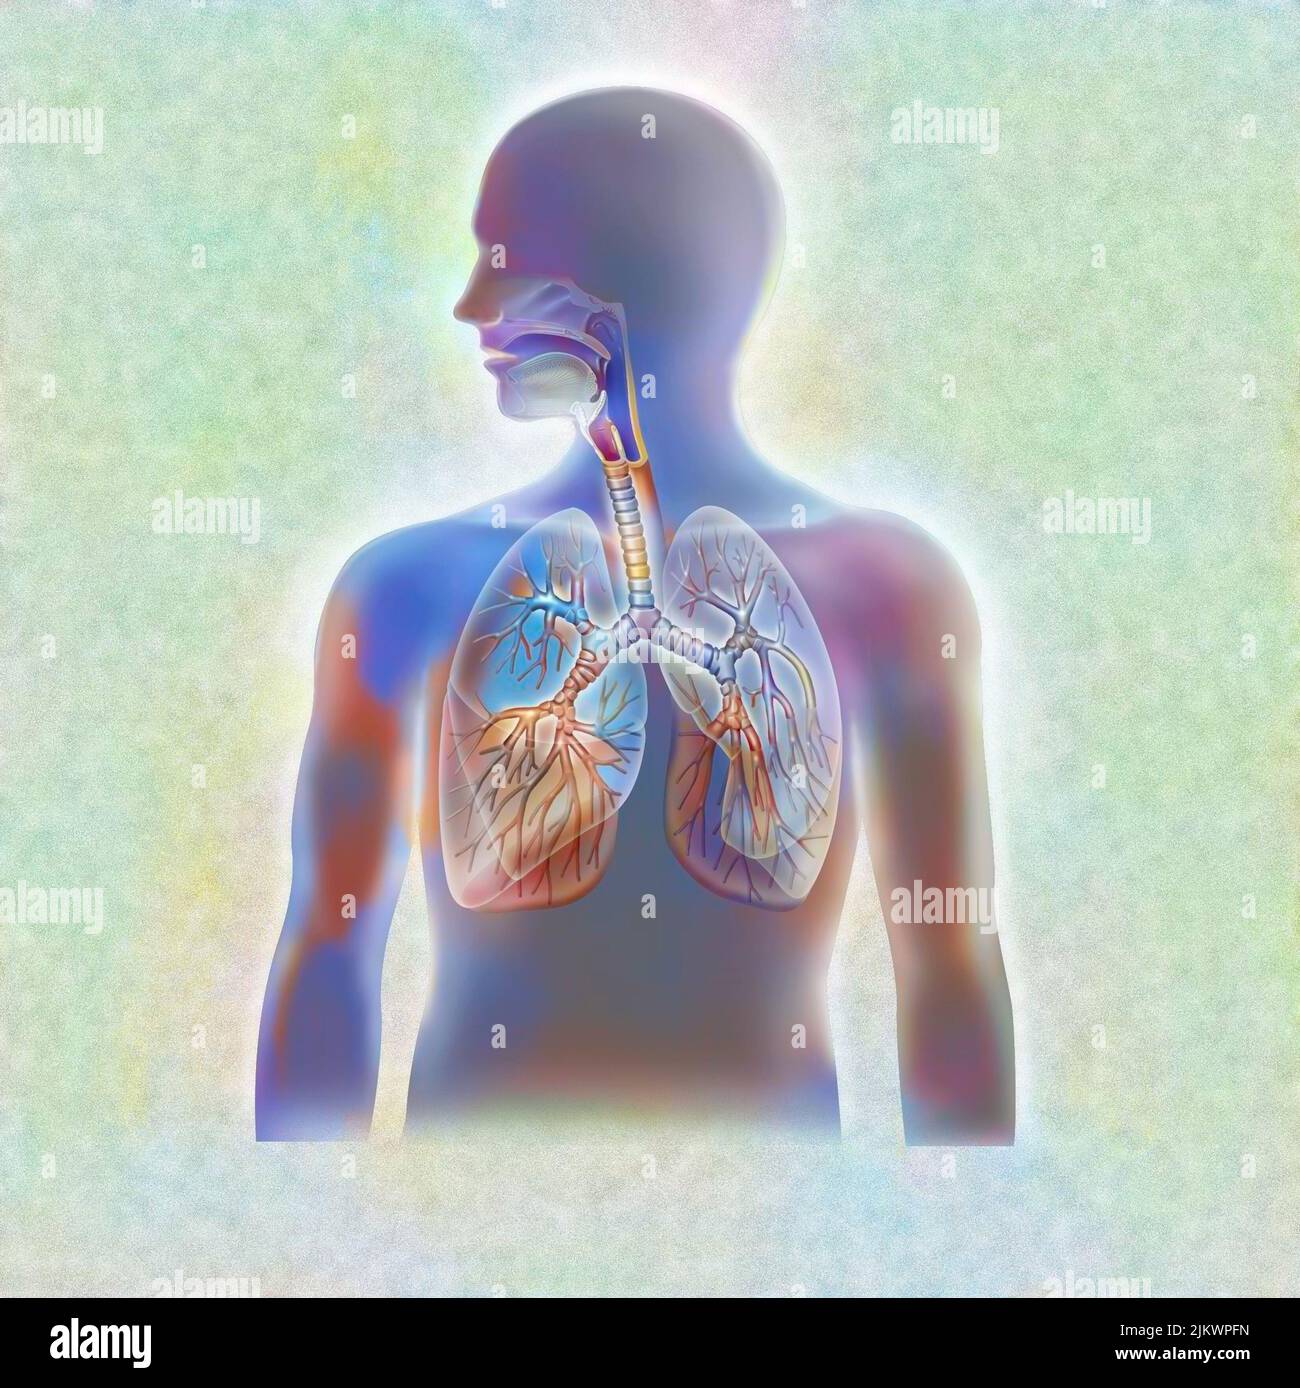

RFDGYRD7–Männliche Anatomie, inneren Organe allein, volle Atmungs- und Verdauungssystem, mit einigen Organen Cutaway. Anatomie-Bild.